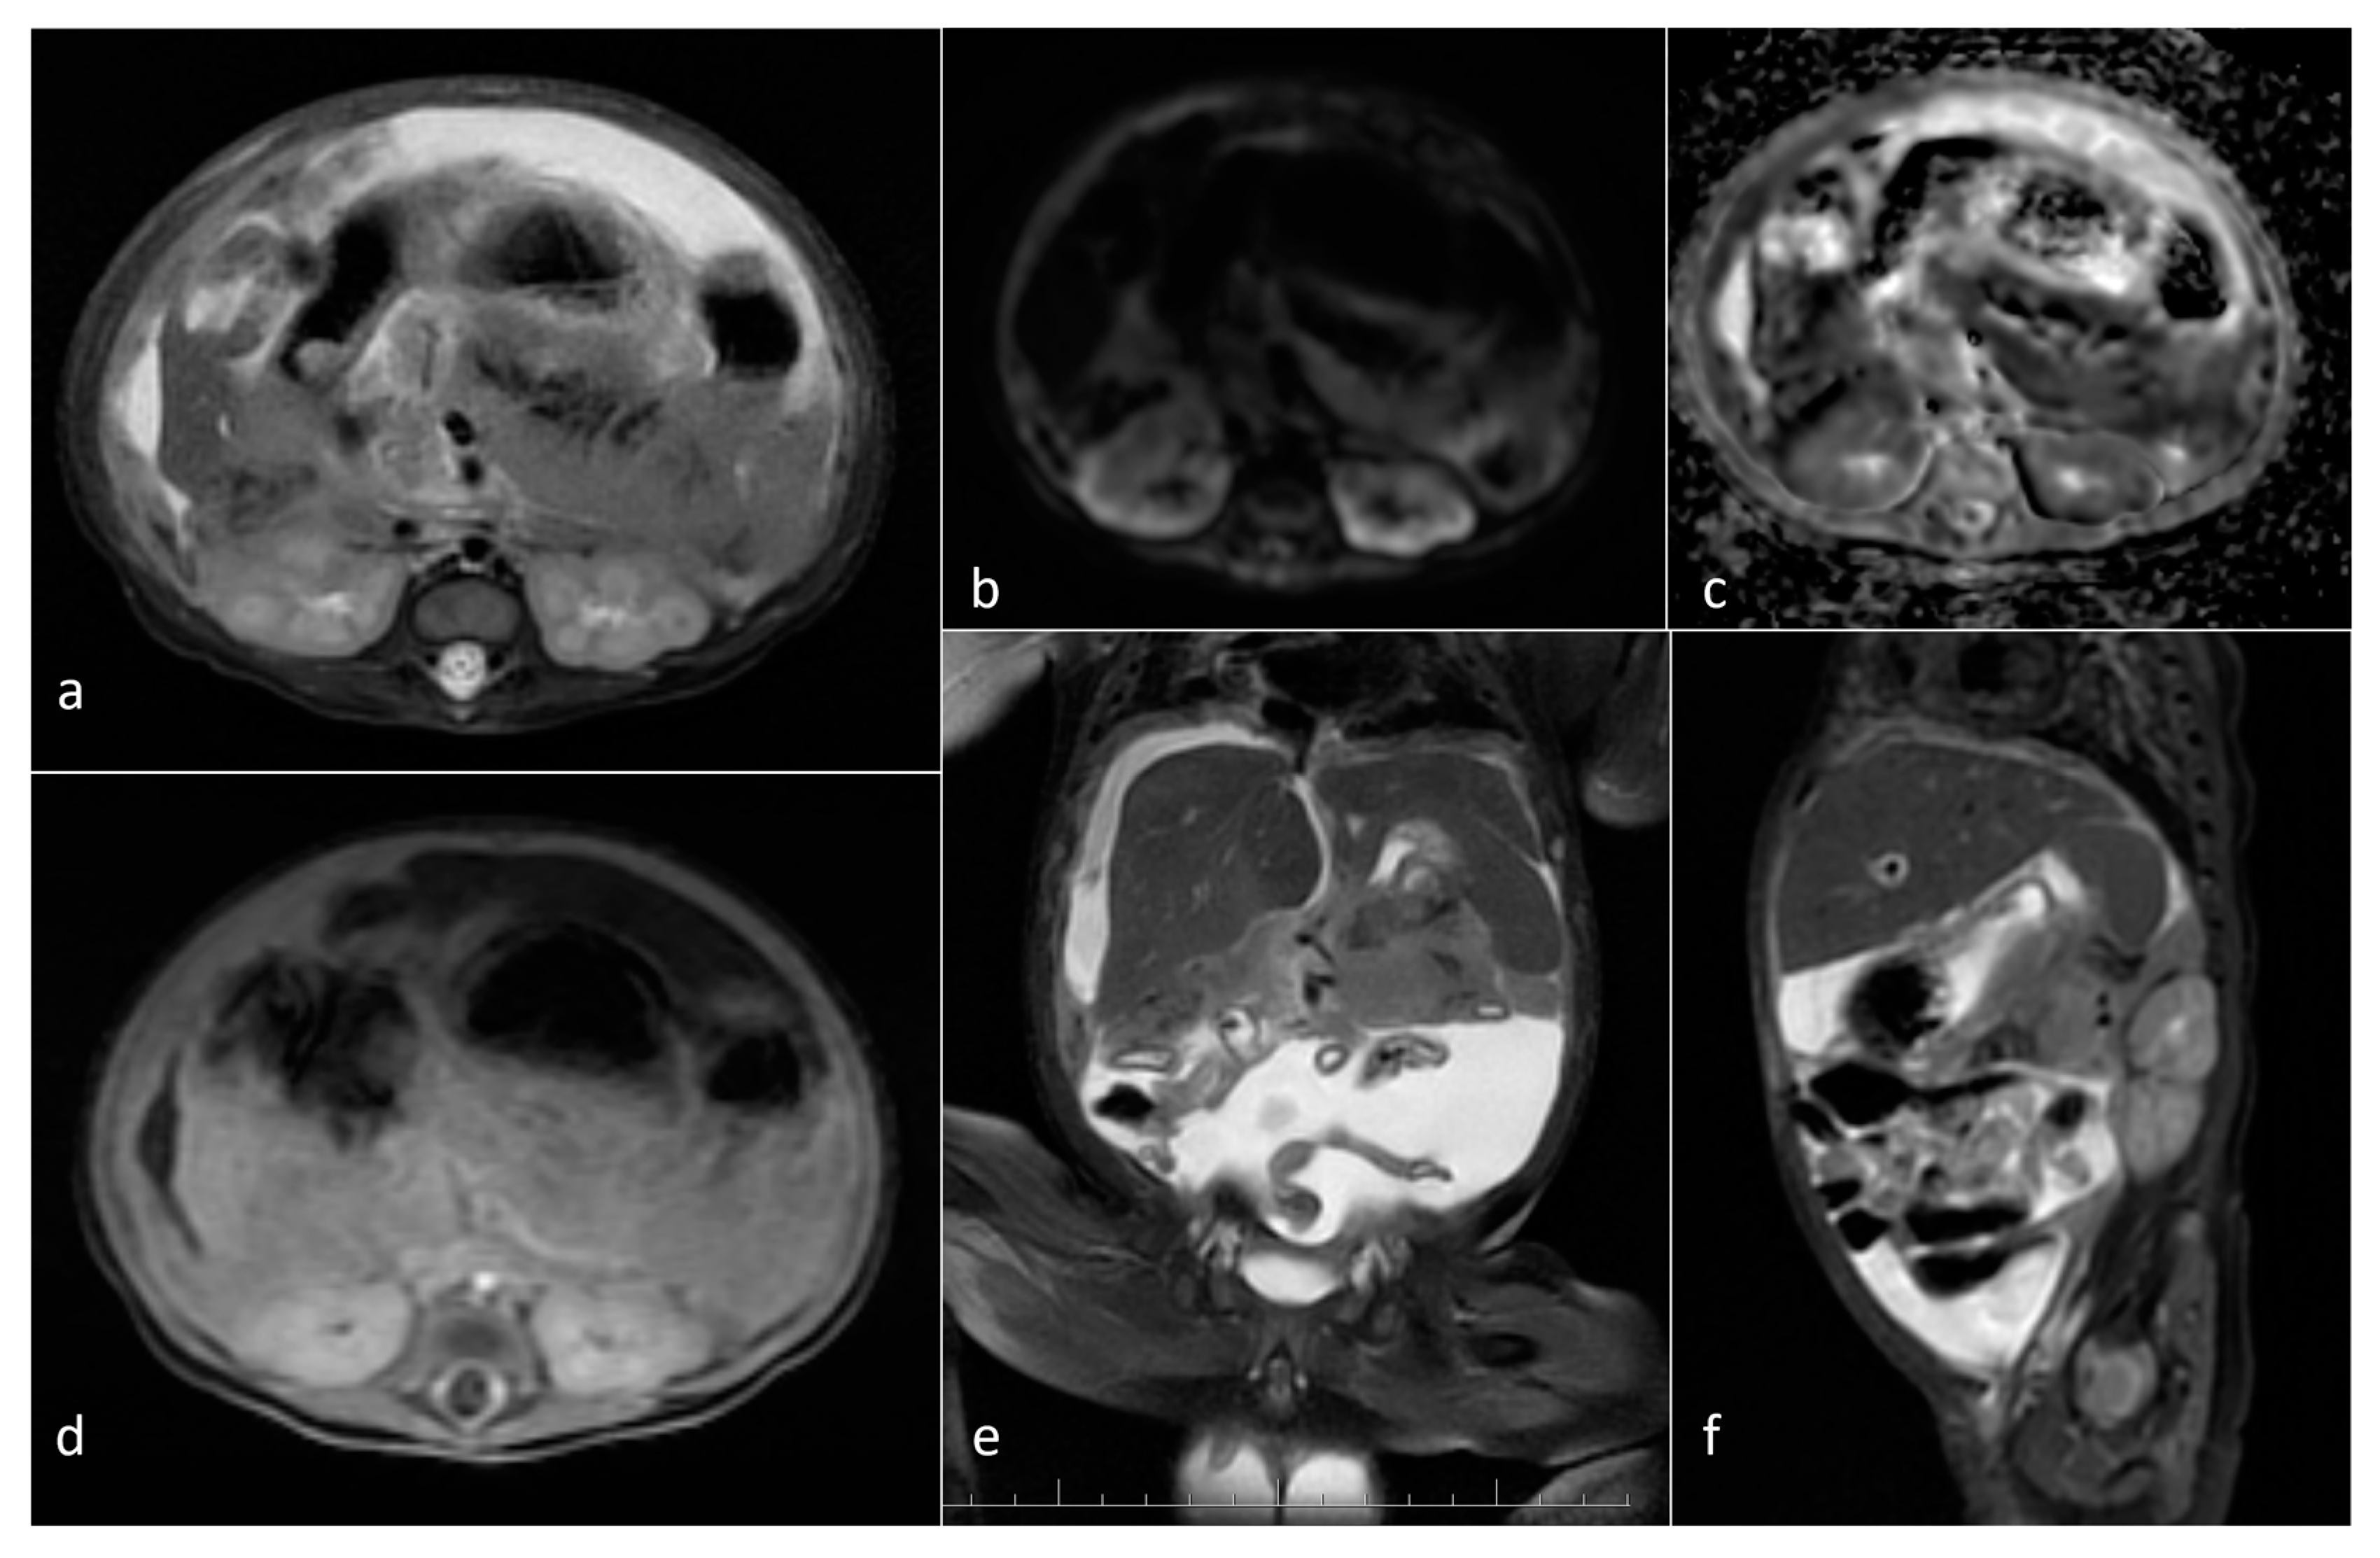

| Neuroblastoma | adrenal gland/infrarenal space | 5 | 11.9 [2.6–24.2] | yes (3/5) (754–1200) | solid/mixed | yes (2/5) | yes (3/3) |

| Mesoblastic nephroma | kidney | 2 | 98.4 [42.9–153.9] | yes (1100–1310) | Solid | 0/2 | yes (1/2) |